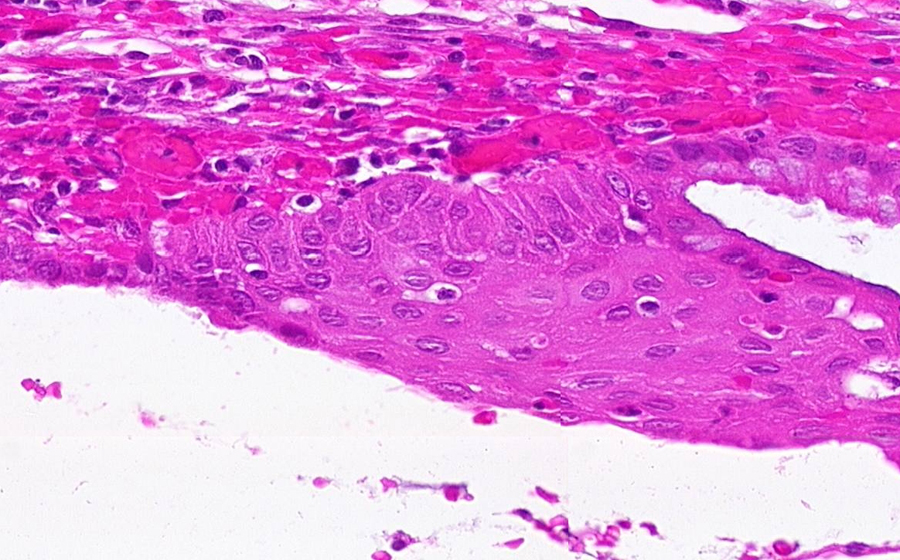

Slide 3: Chronic cervicitis and metaplasia

Histologic section of cervix from a patient with chronic cervicitis (click here to review normal tissue)

Image 4 - 200X

Slide 3 - Image 4